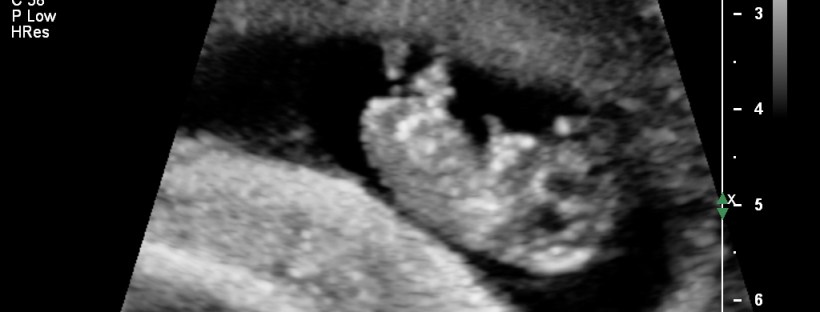

At 15 weeks and 2 days I felt my baby move for the first time. I was 95% sure at the time that that's what I'd felt. I knew that it was a bit early for a first baby however I'm so in tune with my body after the miscarriages that I pretty much … Continue reading Feeling baby’s first kick.